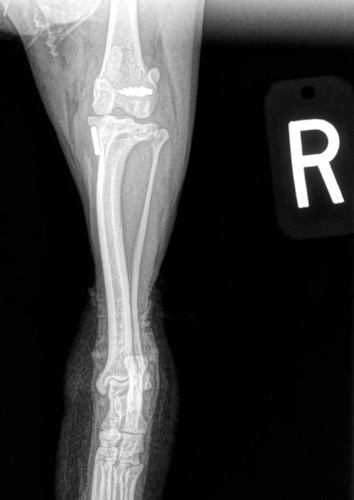

Fore Limb (Humerus, Radius/Ulnar, Metacarpus)

Hind Limb (Pelvis, Femur, Patella, Tibia/Fibula, Lateral Malleolus)

- Fracture Fixation: $4,000 - $8,000+